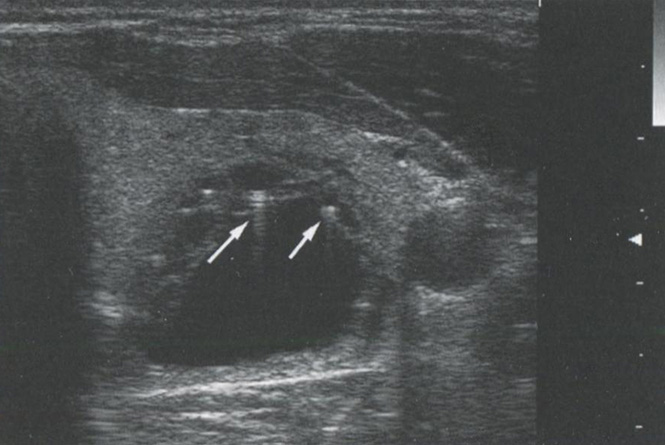

В то же время кистозные структуры проводят звук с очень маленьким затуханием, в результате этого интенсивность звуковых волн за ними намного выше, чем у прилежащих структур. Это приводит к акустическому усилению с ярким сигналом позади кистозных или анэхогенных структур. Это усиление может быть использовано для дифференциации кистозных и солидных узлов в ЩЖ. Рис. 2.12 показывает усиление сигнала.

Рис. 2.12. Усиление сигнала. Кистозные структуры проводят звук с незначительным затуханием, что проявляется в большей интенсивности звуковых волн позади таких образований. Усиление сигнала обычно возникает кзади от кистозного узла

Рис. 2.13. Усиление сигнала. Аденомы паращитовидных желез имеют сравнительно гомогенную ткань и, как кисты паращитовидных желез, могут демонстрировать усиление сигнала позади себя

Однако усиление сигнала происходит не только при наличии кистозных узлов. Любая структура, вызывающая минимальное затухание УЗ-сигнала, будет иметь усиление кзади от себя. На рис. 2.13 продемонстрировано усиление сигнала кзади от солидной аденомы ПЩЖ. На рис. 2.14 показано усиление сигнала позади доброкачественного коллоидного узла. Из-за высокого содержания жидкости и коллоида в узле и, как следствие, уменьшения клеточного компонента затухание сигнала в этом образовании происходит в меньшей степени, чем в окружающей ткани щитовидной железы.